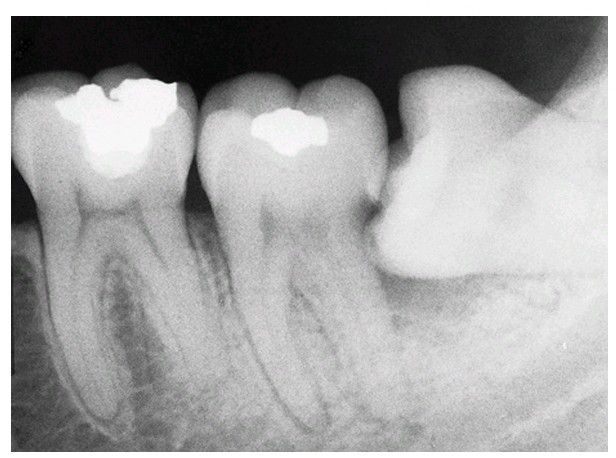

Radiograph of a mandibular third molar impacted against a second molar with bone loss resulting from the presence of a third molar.